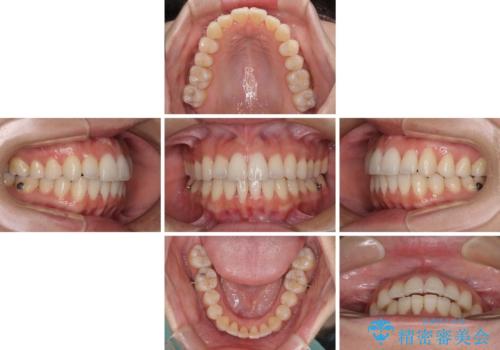

前歯のクロスバイト インビザラインによる矯正治療

- 上下のクロスバイトと前歯のデコボコを気にして来院された患者様です。

インビザラインを用い、IPR(歯と歯の間を削る)と歯列全体を拡大させることで、歯並びを整えていくこととしました。

治療を急いでいらっしゃらなかったため、のんびりと治療を進めていきました。3年以上の期間を要しましたが、きれいな口元に仕上がりました。